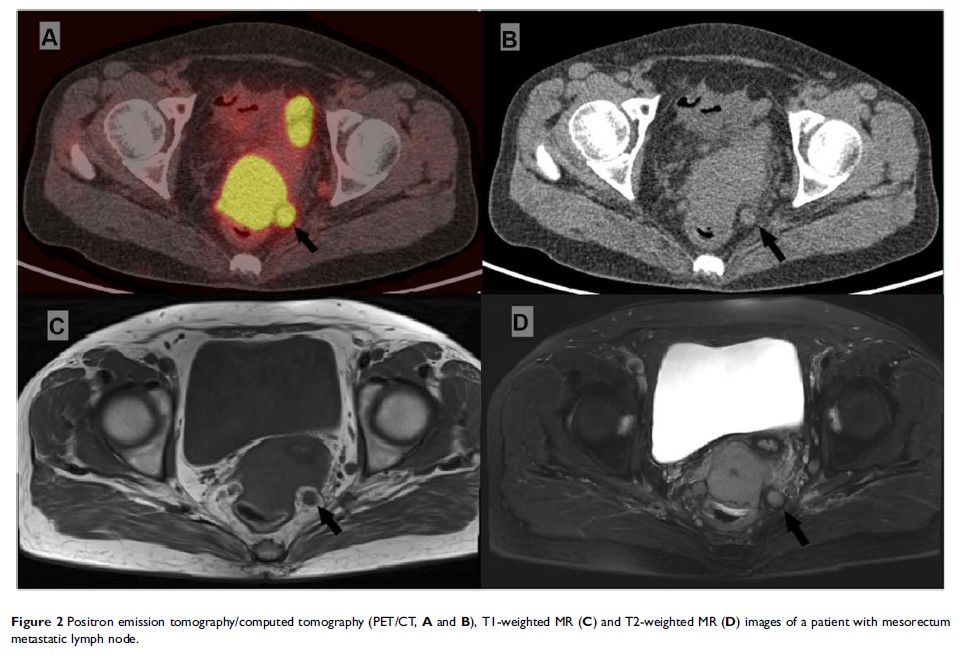

宫颈癌的直肠系膜淋巴结转移患者的特征和生存率